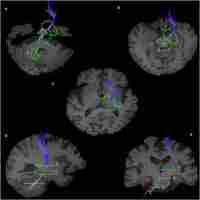

| Abstract | Cerebellar-thalamic connections play a central role in deep brain stimulation-based treatment of tremor syndromes. Here, we used diffusion MRI tractography to delineate the main cerebellar peduncles as well as two main white matter tracts that connect the cerebellum with the thalamus, the dentato-rubro-thalamic tract (DRTT) and the subthalamo-ponto-cerebellar tract (SPCT). We first developed a reconstruction protocol in young healthy adults with high resolution diffusion imaging data and then demonstrate feasibility of transferring this protocol to clinical studies using standard diffusion MRI data from a cohort of Parkinson’s disease patients and their matched healthy controls. The tracts obtained closely corresponded to the previously described anatomical pathways and features of the DRTT and the SPCT. Second, we investigated the microstructure of these tracts with fractional anisotropy, radial diffusivity and hindrance modulated orientational anisotropy in patients with Parkinson’s disease (PD) and healthy controls. Reducing dimensionality of both the microstructural metrics and the investigated cerebellar and cerebellar-thalamic tracts using principal component analyses, we found global differences between PD patients and controls, suggestive of higher fractional anisotropy, lower radial diffusivity and higher hindrance modulated orientational anisotropy in the patients. However, separate analyses for each of the tracts did not yield any significant differences. Our findings contribute to the characterisation of the distinct anatomical connections between the cerebellum and the diencephalon. Microstructural differences between patients and controls in the cerebellar pathways suggest involvement of these structures in PD, complementing previous functional and diffusion imaging studies. |